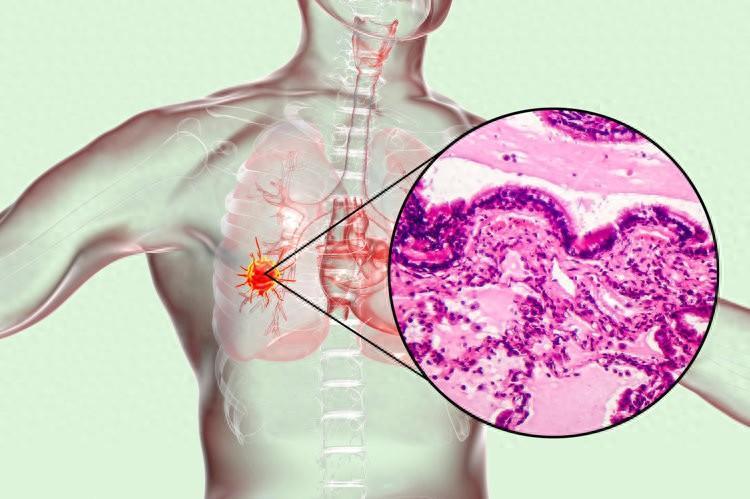

近段時間被頻繁的咳嗽、胸痛困擾,劉叔只好去了醫院,結果發現之前的結節變大了,醫生便趕緊給他安排了手術,病理顯示浸潤性腺癌,好在發現及時並處理了。

雖然治癒出院了,但劉叔還是想不通自己一個小小的結節,怎麼就成癌症了?那是不是結節都會發生癌變呢?

一、結節會癌變嗎?體檢查出結節應該怎麼辦

結節其實是人體內體積較小的一種腫物,可發生於人體的任何部位,由於如今的CT分辨率越來越高,因此結節的檢出率也變高了。

上海市胸科醫院住院醫師李博斐介紹:根據結節的位置不同,有甲狀腺結節、肺結節、乳腺結節等不同分類,多數結節是良性的,只有少數是惡性的。